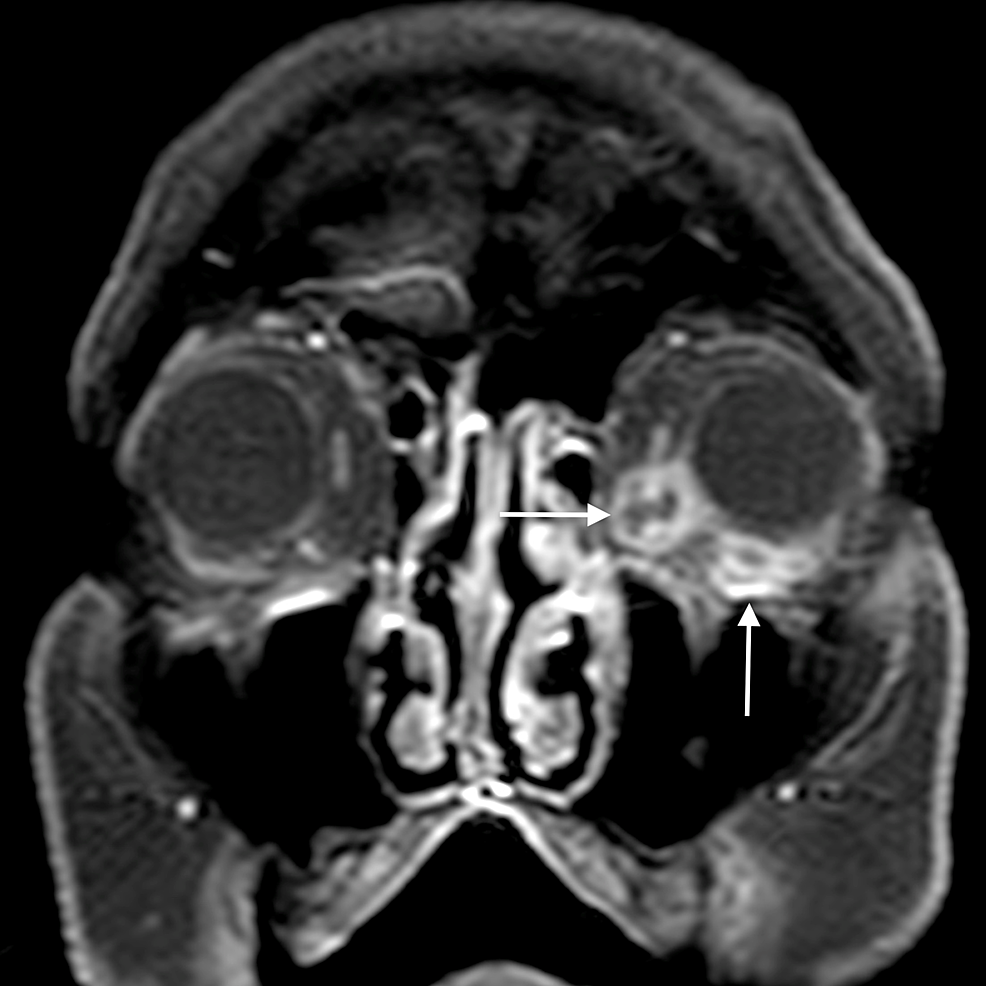

The main complications of orbital cellulitis (Figures 2-4) encountered in our study were:

1. An orbital abscess (Figures 5-6);

2. Preseptal cellulitis and abscess (Figures 7-8);

3. Periorbital cellulitis (Figures 9-10);

4. Dacryoadenitis (Figures 11-12);

5. Optic neuritis/perineuritis (Figure 13);

6. Cavernous sinus thrombophlebitis and thrombosis (Figure 14).

The most common complication of orbital cellulitis was orbital/periorbital abscess formation (eight cases, 53.3%), followed by optic neuritis (four cases, 26.67%), intracranial involvement (four cases, 26.67%), dacryoadenitis (three cases, 20%) and cavernous sinus thrombophlebitis (three cases, 20%).